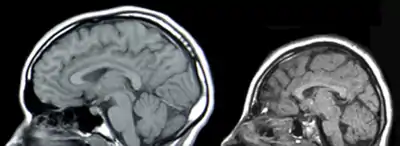

Мікроцефалі́я (від грец. μικρός — маленький і κεφαλή — голова) — медичний стан, при якому головний мозок не розвивається належним чином, внаслідок чого розмір голови є меншим від нормального.[1] Мікроцефалія може бути вродженою або розвинутися в перші кілька років життя.[1] На сьогодні немає достовірних тестів, за допомогою яких можна було б заздалегідь виявити цю патологію, але ультразвукове дослідження мозку плода в третьому триместрі вагітності іноді може виявити цю проблему[2].

Визначають мікроцефалію вимірюванням окружності голови, і якщо вона на два стандартних відхилення менша від окружності середньої для даного віку та статі, це свідчить про мікроцефалію,[4][5] хоча деякі науковці вважають, що окружність голови має бути на три стандартних відхилення меншою від середньої для даного віку та статі.[6]